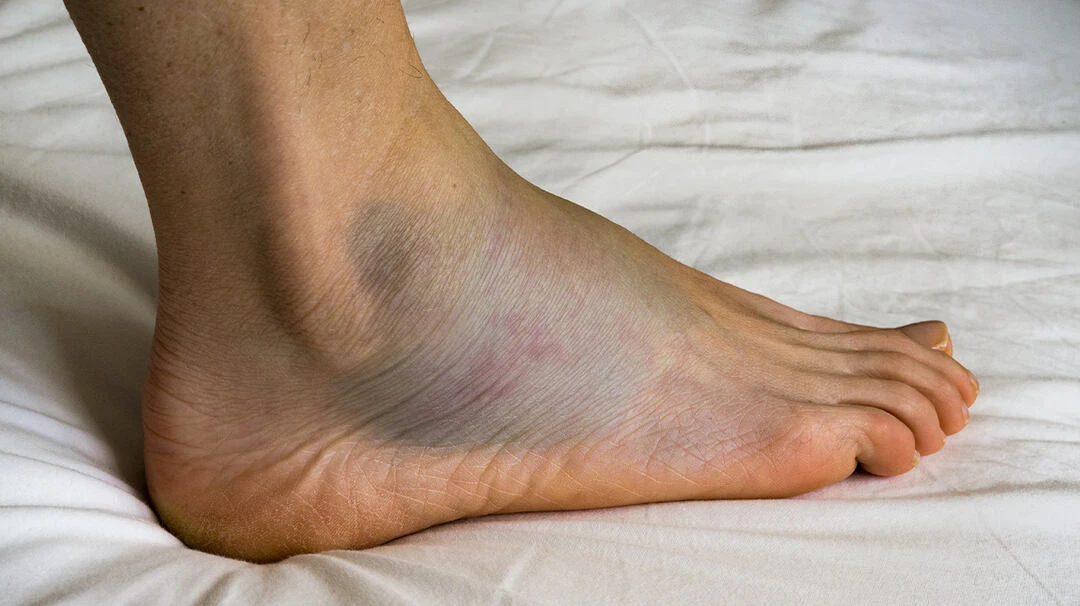

Gãy chân thường gây ra tình trạng phù nề (Ảnh minh họa internet)

Bệnh nhân không thể hoạt động bình thường ở bên chân bị gãy. Tại vị trí gãy rất đau và có xuất hiện bầm tím.

- Cẳng chân sưng phù nề nhiều tại vị trí gãy

- Nếu không kịp thời sơ cứu và điều trị, vị trí gãy gia tăng mức độ phù nề và có các nốt phỏng huyết thanh